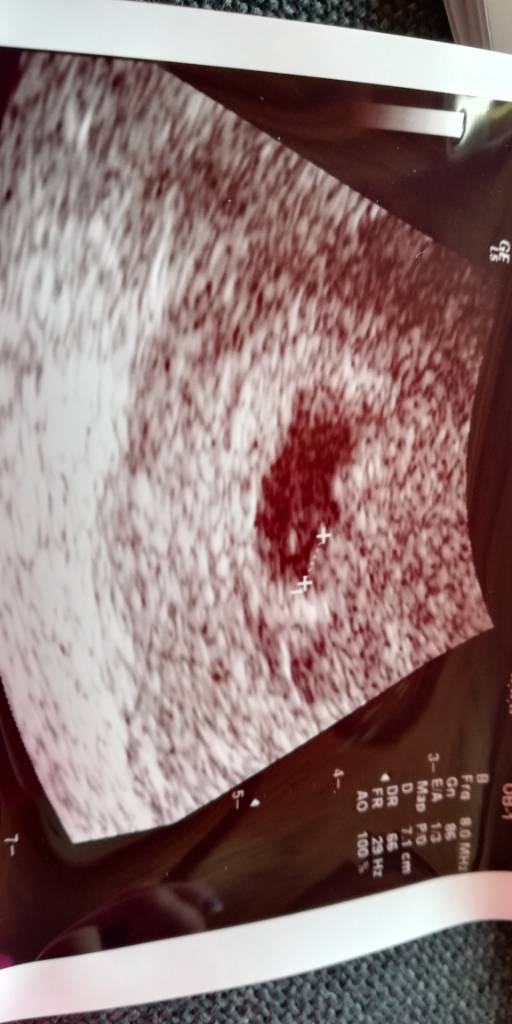

A to moje 3 mm. szczęście :) Zobacz załącznik 1018491